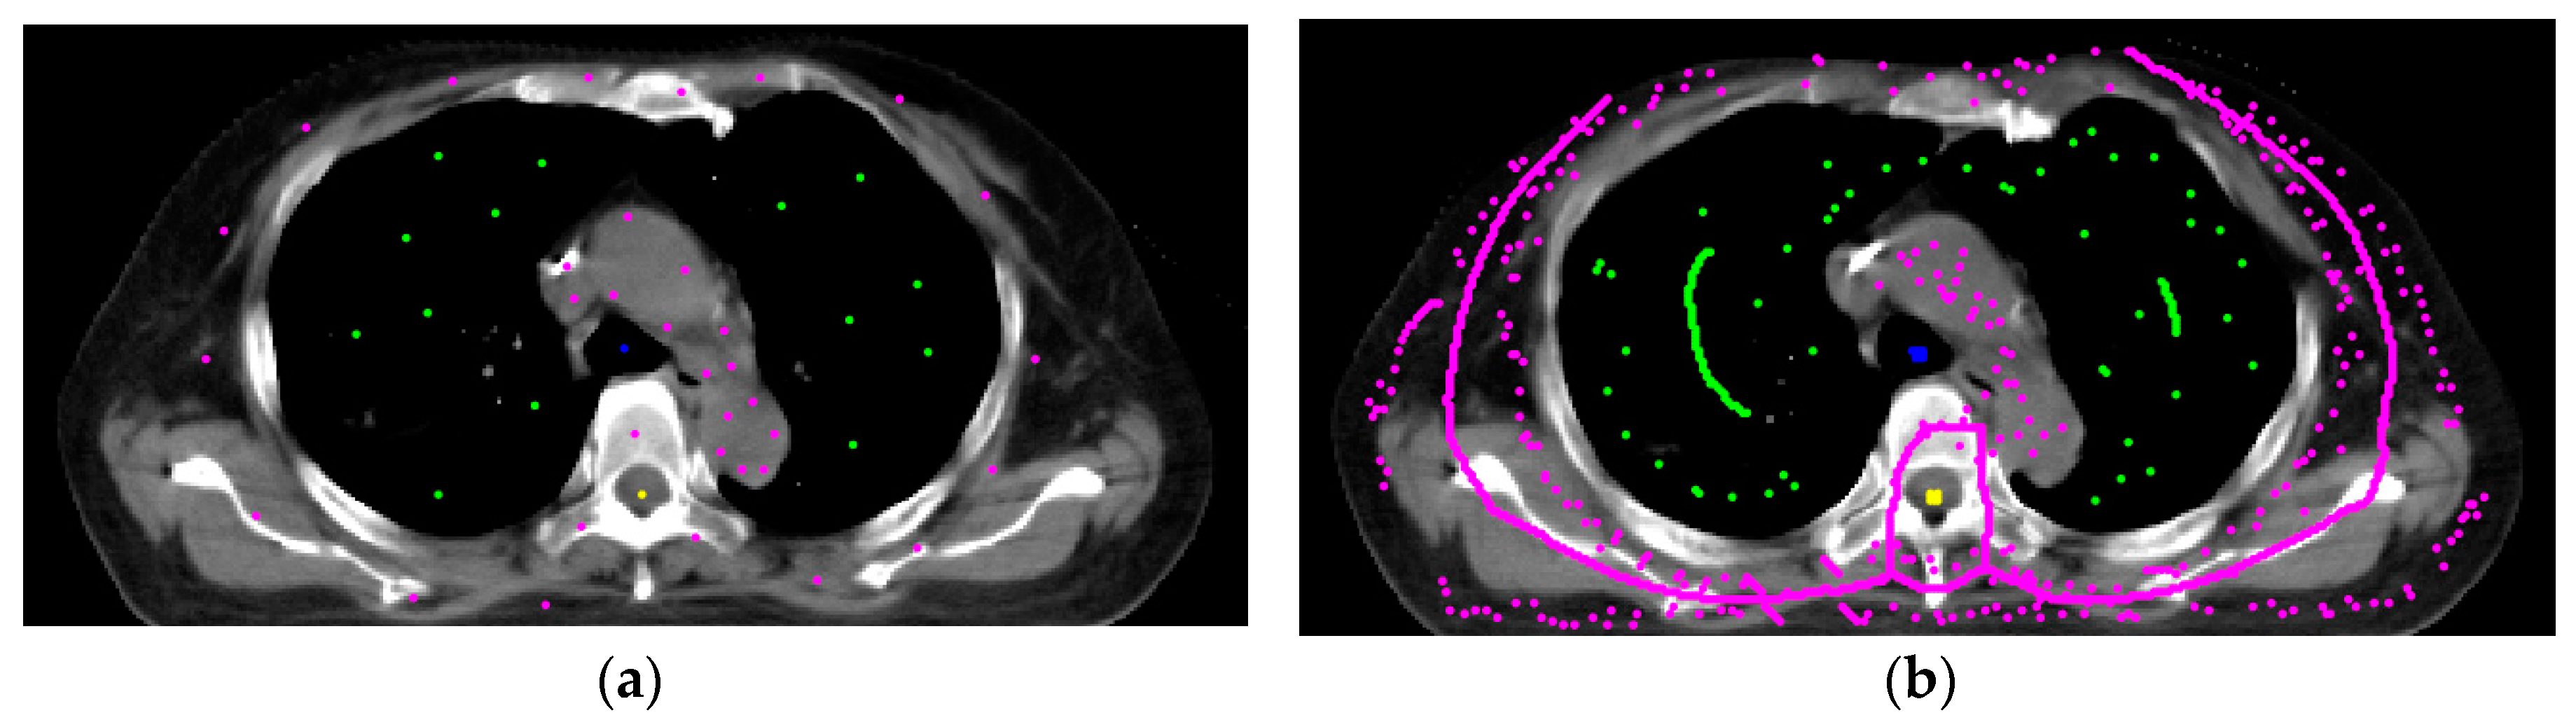

2.5. Use of the Skeleton Technique to Produce Seeds

2.6. Modification of the Spinal Cord Boundary

3.1. Initial Settings

3.2. Automated Segmentation